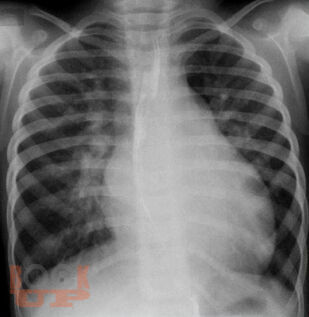

В пособии представлены общие сведения о врожденных и приобретенных пороках сердца, изложены этиология, механизмы нарушений гемодинамики, клинические особенности, данные объективного исследования, диагностические тесты и принципы терапии пороков сердца, дана информация об искусственных клапанах сердца, продемонстрированы особенности ведения беременности при пороках сердца.

Учебное пособие хорошо иллюстрировано, предназначено для студентов старших курсов медицинских вузов, практических врачей.